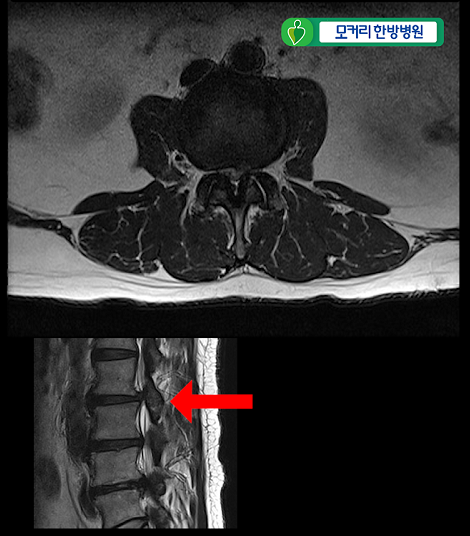

<4-5번>

이 환자분은 협착증을 25년간 앓으시고 증상도 매우 심하신 환자분입니다.

허리 세 마디 2번 3번, 3번 4번, 4번 5번, 이렇게 세 마디의 척추관이 심하게 막혀 있습니다.